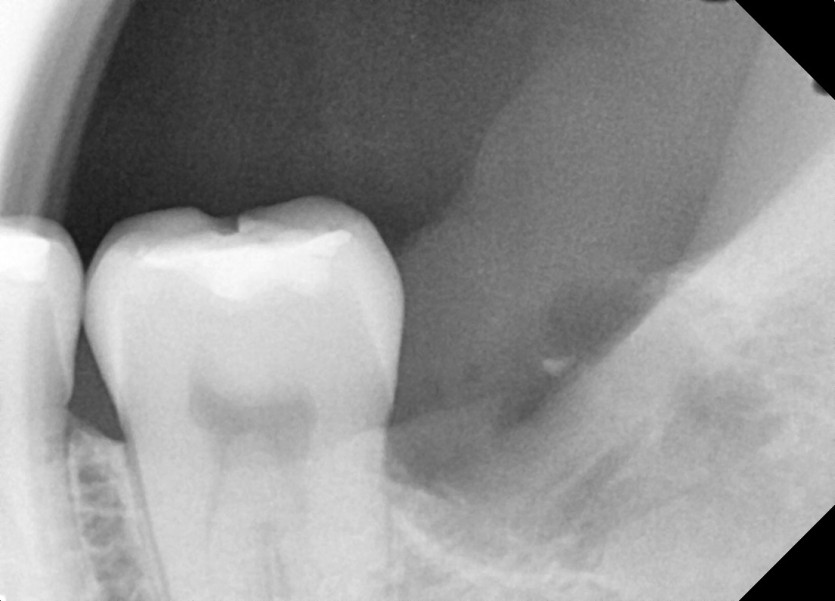

#28,38 사랑니 발치

구강 외과 전문의가 당일 발치하였습니다.